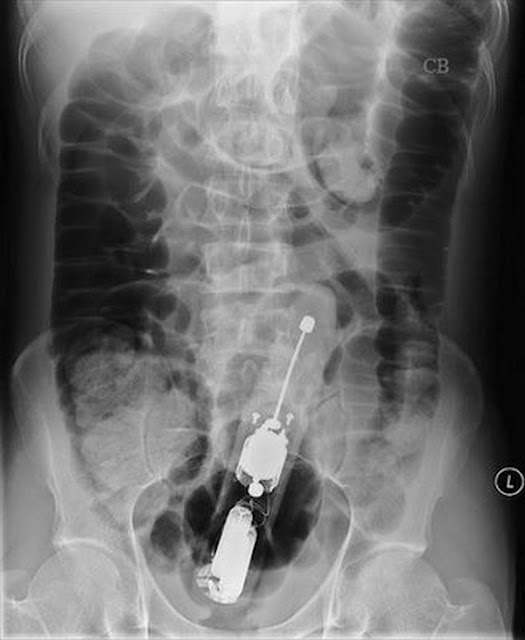

Foto X-Ray Objek Aneh Tertinggal Dalam Organ Intim

mak aihhh,apesal botol spray pn ade kt dlm tu  |

Mak aiii tin hair spray pun ada |